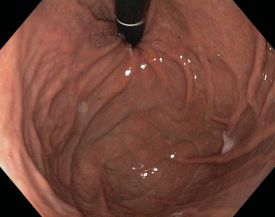

Bei der Gastroskopie (Magenspiegelung) wird der Magen mit Hilfe eines schlauchförmigen Gerätes von innen untersucht. An dessen Spitze befindet sich ein hochauflösender Videochip. Damit lassen sich außer dem Magen auch die Speiseröhre (Ösophagus) und der Zwölffingerdarm (Duodenum) betrachten, so dass man die Untersuchung häufig auch als Ösophago-Gastro-Duodenoskopie, abgekürzt ÖGD, bezeichnet.

Die Untersuchung erfolgt mit einem so genannten Gastroskop, einem steuerbaren, flexiblen Schlauch, der an ein Videosystem angeschlossen ist.

Die von uns verwendeten modernen Gastroskope haben einen Durchmesser von weniger als einem Zentimeter.

Während der Patient auf der linken Seite liegt, wird das Gastroskop über den Mund in die Speiseröhre eingeführt und weiter in den Magen und Zwölffingerdarm geschoben. Zur besseren Sicht wird Luft in den Magen eingeblasen.